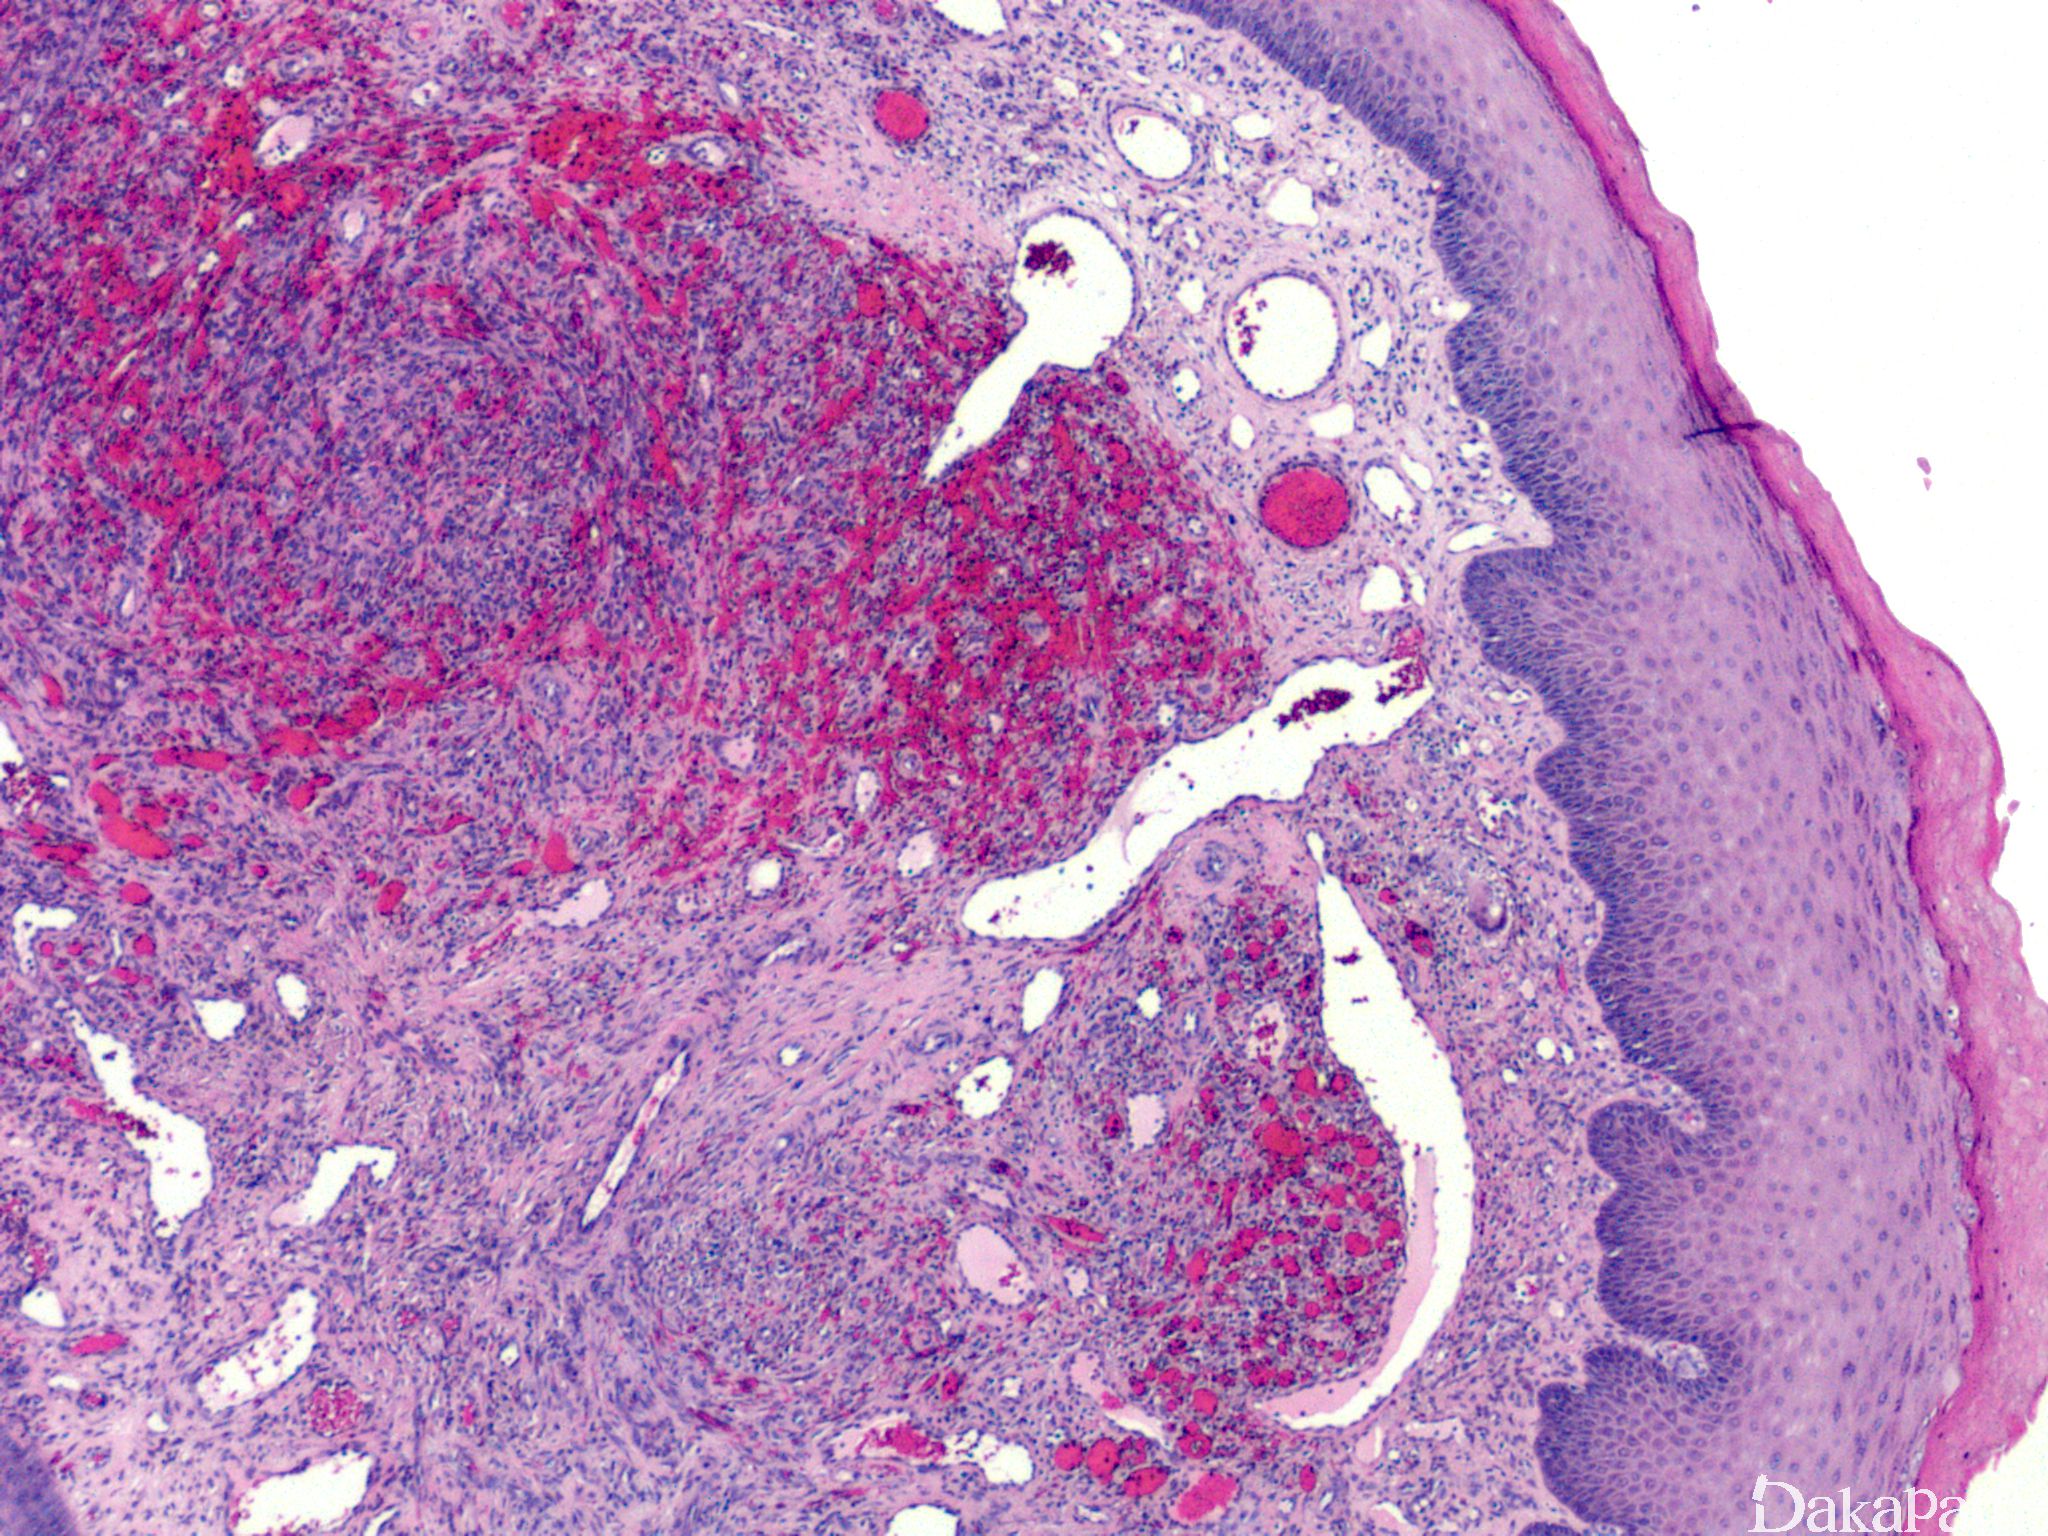

IV 期为结节期:结节期的病变边界清楚,主要由网状或裂隙状的毛细血管及其周围纵横交错的嗜酸性梭形细胞组成,梭形细胞有一定异型性,核分裂偶见;梭形细胞和血管之间为含有红细胞的裂隙,横切面呈筛孔状或蜂窝状,在梭形细胞内或细胞外可见抗淀粉酶消化 PAS 阳性的嗜伊红色透明小体,结节的边缘常见炎症细胞浸润、含铁血黄素沉着和扩张的血管。 典型的卡波西肉瘤细胞无明显的异型性,核分裂像也不多见,但少数病例中瘤细胞分化较差,异型性明显,可见较多的核分裂像。

- 银染见网状纤维分布于梭形细胞之间并围绕血管腔隙